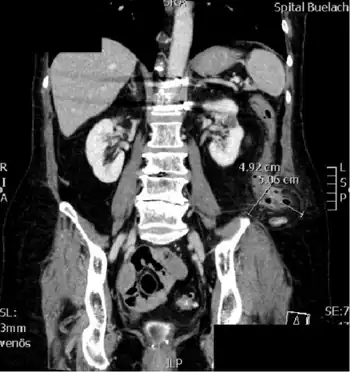

Image-perforated sigmoid colon in a left lumbar hernia, classified as Petit's hernia